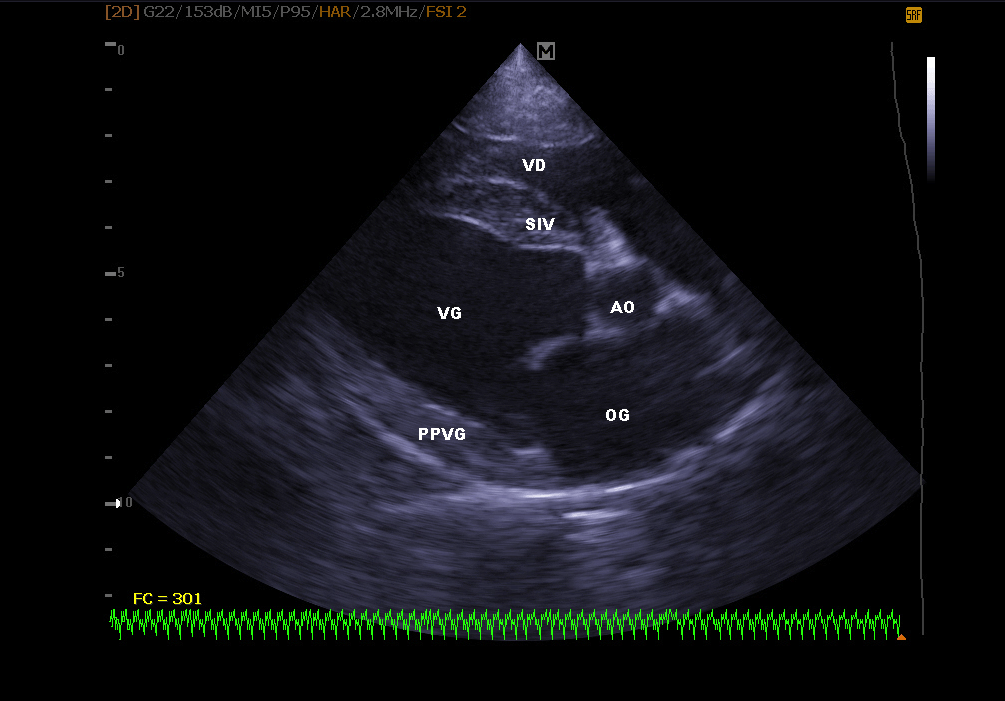

Echocardiography:

It makes it possible to visualize the different parts of the heart (walls, cavities, valves) and to identify any anomalies that prevent correct cardiac functioning. In case of heart failure, echocardiography also allows regular monitoring of cardiac morphology. It is then easier to readjust the treatment in place.